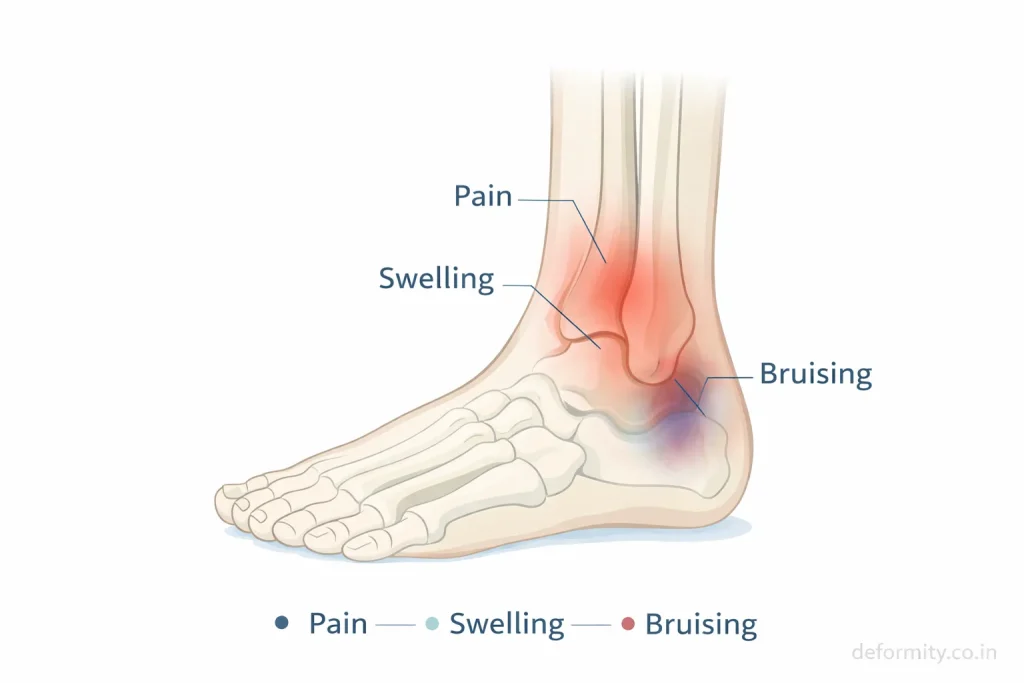

Symptoms of Lateral Malleolus Fracture

Symptoms vary depending on severity and displacement.

Common symptoms include:

- Pain on the outer side of the ankle

- Swelling around the ankle

- Bruising

- Difficulty bearing weight

- Tenderness over the fibula

- Reduced ankle movement

Severe fractures may cause deformity or inability to stand. Persistent pain after ankle injury should always be evaluated with imaging.